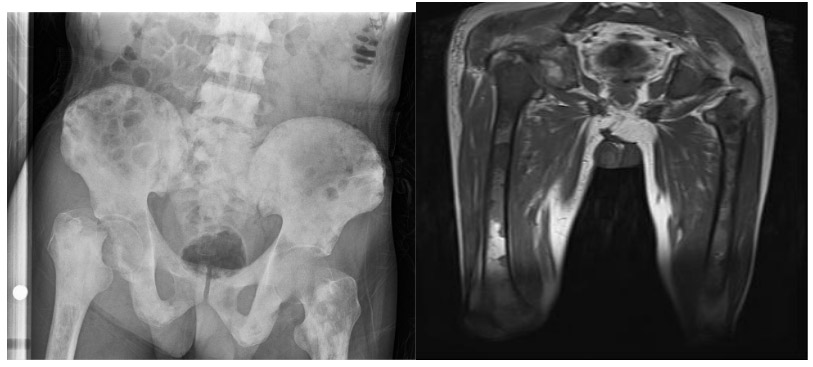

CASE 25: Fracture due to prostate cancer metastasis to the right hip (femoral neck).

Before the surgery: X-ray and MRI show a femoral neck fracture and multiple bone metastases.